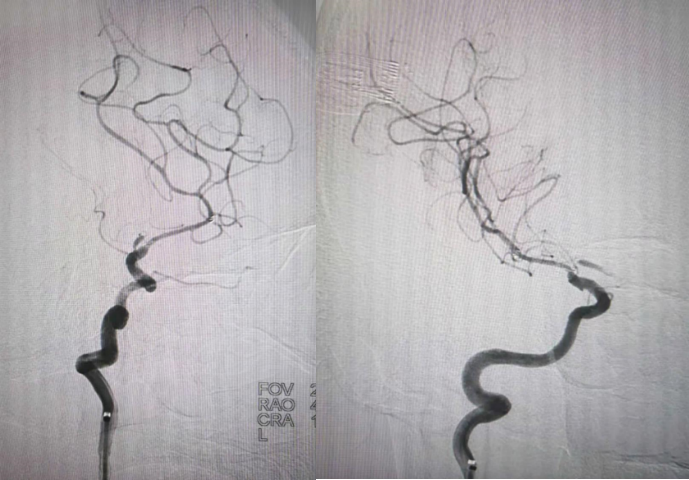

赛诺球囊扩张(1.5 mm×15 mm)

赛诺球囊扩张后狭窄有所改善但管壁不光滑

药物球囊扩张(2.0 mm×20 mm)

药物球囊扩张后

药物球囊扩张后10分钟狭窄明显改善且血管壁较光滑